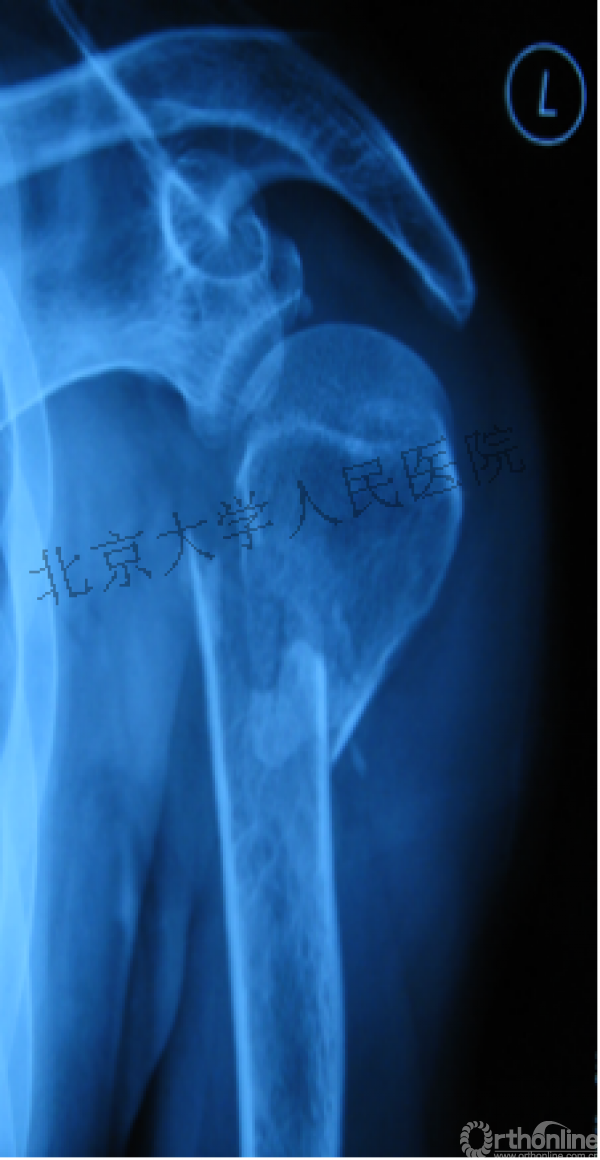

另一个留有遗憾的病例,您的选择?PHN?

临床中的广泛内固定治疗不断地提出思考